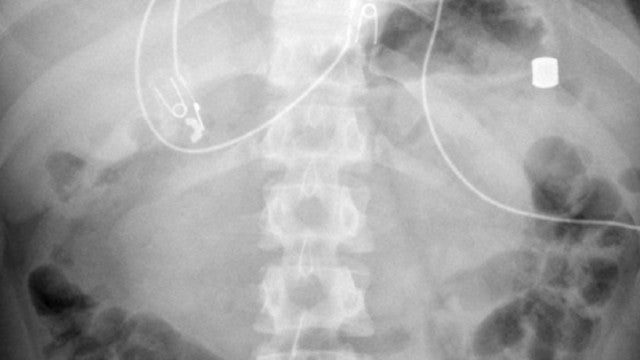

Um adolescente de 13 anos deu entrada nas urgências de um hospital nos Estados Unidos com fortes dores abdominais. Após uma série de exames, os médicos descobriram que ele tinha 21 ímãs no estômago e intestinos.

De acordo com o site BMJ Case Reports, o paciente tinha “múltiplos corpos estranhos metálicos” no estômago e cólon, com diâmetros de cerca de 8 milímetros.

Para ser submetido a mais exames, o jovem foi transportado para outro hospital, onde novas radiografias confirmaram que se tratava de ímãs de neodímio.